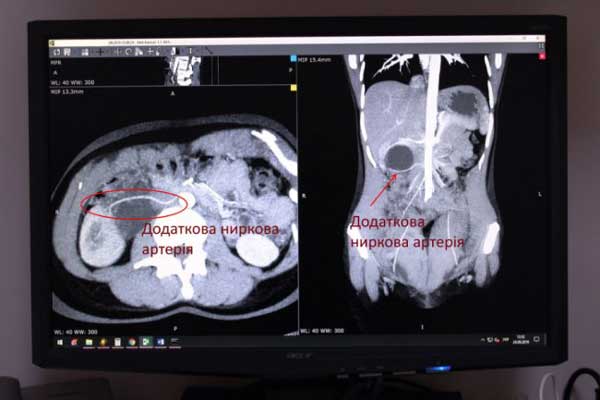

У Ковельському МТМО урологи успішно здійснили операцію на нирці, яку в медицині вважають вищим пілотажем - лапароскопічна резекція додаткової ниркової артерії з резекцією миски правої нирки та антеградним стентуванням сечовода.

Медики кажуть, що пацієнтка була направлена на комп'ютерну томографію з єдиною скаргою – ниючий біль в попереку справа, який турбував останні півроку. В результаті дослідження у жінки виявили синдром Фролея (вроджена аномалія розвитку ниркових артерій) та гідронефроз.